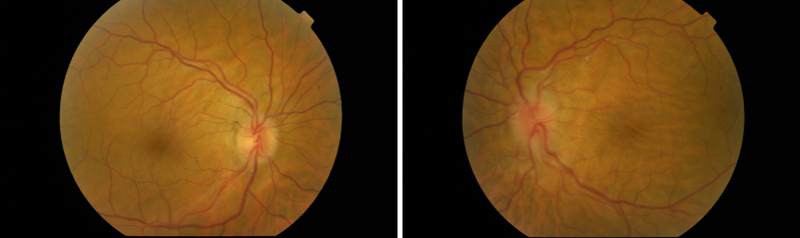

- Síndrome de Vogt-Koyanagi-Harada: en este caso la inflamación ocular es bilateral pero asimétrica y clínicamente se presenta de manera similar a la escleritis posterior6. Recientemente se ha demostrado mediante OCT de alta resolución que la presencia de pliegues coroideos se relaciona con el mayor engrosamiento de la coroides en la fase aguda de la enfermedad y, que a su vez se relaciona con una mayor duración del episodio inflamatorio9 (Figura 8).

Figura 8. Pliegues coroideos bilaterales en la fase uveítica aguda de una paciente de 40 años con la enfermedad de Vogt-Koyanagi-Harada. En las retinografías destaca la presencia de múltiples focos de desprendimientos serosos localizados en polo posterior y el edema de papila en ambos ojos.